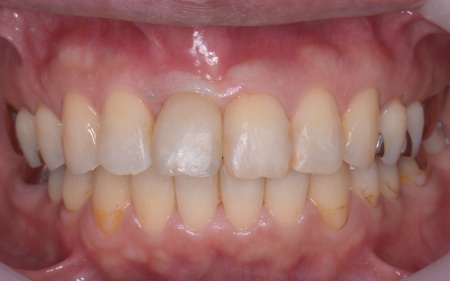

歯並びが十分に整ったあとは、インプラントに装着する被せ物を作製します。

被せ物の素材には、強度と自然な見た目を兼ね備えているセラミックを採用し、隣接する天然歯との色調や形態を精密に調整して、違和感のない自然な仕上がりを実現しました。

最後に、完成したセラミックの被せ物を装着し、見た目や噛み合わせ、使用感に問題がないことを確認して、治療を終了しています。